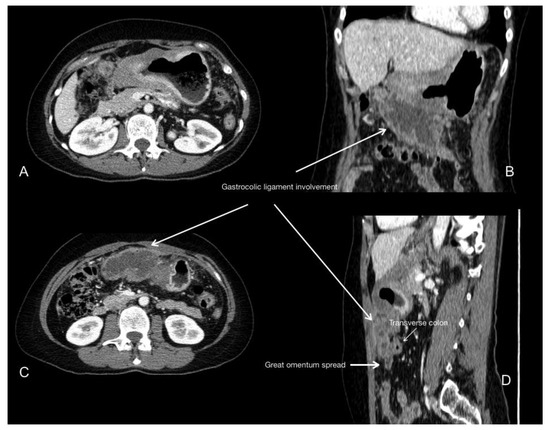

- Young, J.J.; Pahwa, A.; Patel, M.; Jude, C.M.; Nguyen, M.; Deshmukh, M.; Huang, L.; Mohammad, S.F. Ligaments and lymphatic pathways in gastric adenocarcinoma. Radiographics 2019, 39, 668–689. [Google Scholar] [CrossRef] [PubMed]

- Sugarbaker, P.H.; Sardi, A.; Brown, G.; Dromain, C.; Rousset, P.; Jelinek, J.S. Concerning CT features used to select patients for treatment of peritoneal metastases, a pictoral essay. Int. J. Hyperth. 2017, 33, 497–504. [Google Scholar] [CrossRef] [PubMed]